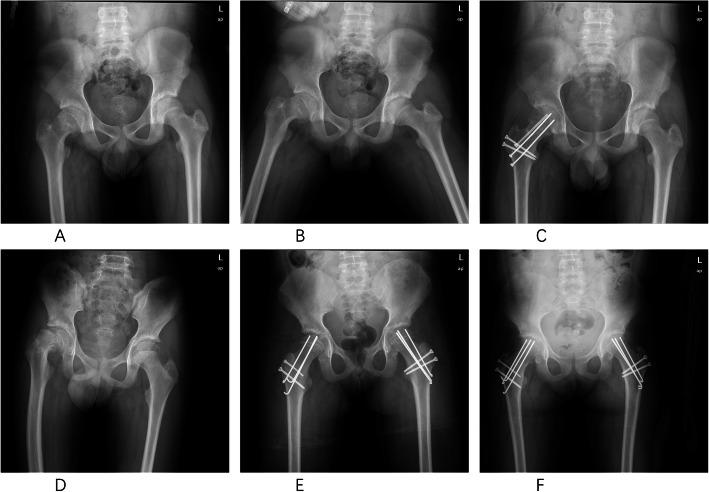

We retrospectively assessed the outcomes of all twenty patients who had been treated with the modified Dunn procedure in our tertiary-care institution. According to the Loder and Fahey criteria, all cases were classified as severe slips; nineteen cases were stable, and one case was an unstable slip. All surgical procedures were performed by one senior orthopedic surgeon who had specific training in the modified Dunn procedure. Operative reports, outpatient records, follow-up radiographs, and the intraoperative findings were reviewed to determine the demographic information, type of fixation, final slip angle, presence of avascular necrosis (AVN), and any additional complications. The mean age of the patients was 13.2 ± 1.6 years (range, 10 to 17 years). Twenty patients (twenty-one hips) with a mean of 31.2 ± 14 months (range, 12 to 57 months) follow-up met the inclusion criteria. Pain and function were assessed by the modified Harris score and WOMAC score. Radiographic anatomy was measured using the slip angle and α-angle. The radiographic findings related to the anatomy of the femoral head-neck junction, as well as signs of early-onset of osteoarthritis (OA) and AVN, were evaluated pre- and postoperatively.

RESULTS

Overall, nineteen patients had excellent clinical and radiographic outcomes with respect to hip function and radiographic parameters. One patient (5%) who developed implant failure at 3 months postoperatively had a poor outcome. The mean preoperative slip angle was corrected from 63.2 ± 8.1° (range, 51 to 84°) to a normal value of 7.5 ± 3.5° (range, 2 to 15°) (p < 0.01). The mean α-angle was improved from an average of 94.5 ± 21.1° (range, 61 to 123°) to postoperative 42 ± 6.4° (range, 25 to 55°) (p < 0.01). The mean modified Harris hip and WOMAC scores postoperatively were 96.7 ± 13.4 (range, 40 to 100) and 95.4 ± 10.6 (range, 38 to 100), respectively. There were no cases of the development of femoroacetabular impingement (FAI) and the progression of OA. We did not record any case of AVN, closure of the growth plate, heterotopic ossification (HO), trochanteric nonunion, or limb length discrepancy that occurred postoperatively either at the most recent follow-up.